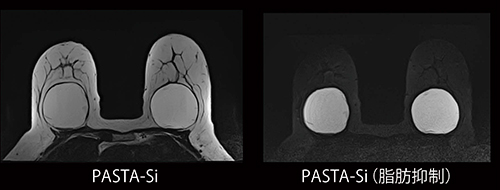

ブレスト・インプラント検査用アプリケーション“PASTA-Si”は,シリコンと脂肪を選択励起して,シリコンを高信号に描出することが可能です。インプラントの内容成分がシリコンであるのか生理食塩水であるのかの識別,さらにはシリコンの漏れの有無を正確に確認することができます(図1)。従来は,手動で中心周波数をシリコンに合わせて高信号化していました。PASTA-Siは,装置が自動でシリコンに周波数を合わせるため,どなたでも簡単にインプラントの検査を行うことが可能です。

図1 シリコンインプラント画像